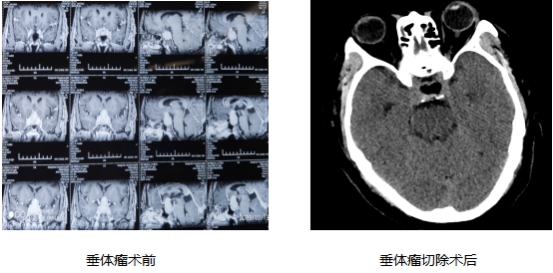

62岁的王先生,3年前出现头昏、头痛,双眼视物模糊等症状。今年下半年,视力进行性下降,严重影响日常生活,3个月前于广元市某医院行头部MRI检查,考虑为大垂体腺瘤,随后经省内知名医院专家会诊后,建议行显微镜下经鼻切除肿瘤。

10月19日,北京天坛医院桂松柏教授及刘春晖教授亲自为患者进行术前评估,术中操作及术后管理指导。高清内镜下,隐藏在死角里的肿瘤一览无余,术野暴露清晰,视野开阔,仅用时1小时20分钟便将深藏在脑垂体里的肿瘤完全切除。术后24小时,患者便可以下床行走,视力及视野无任何损伤。王先生激动的说,没想到在自己家门口,就能享受到如此高水平的医疗服务。

内镜下垂体瘤切除术术中